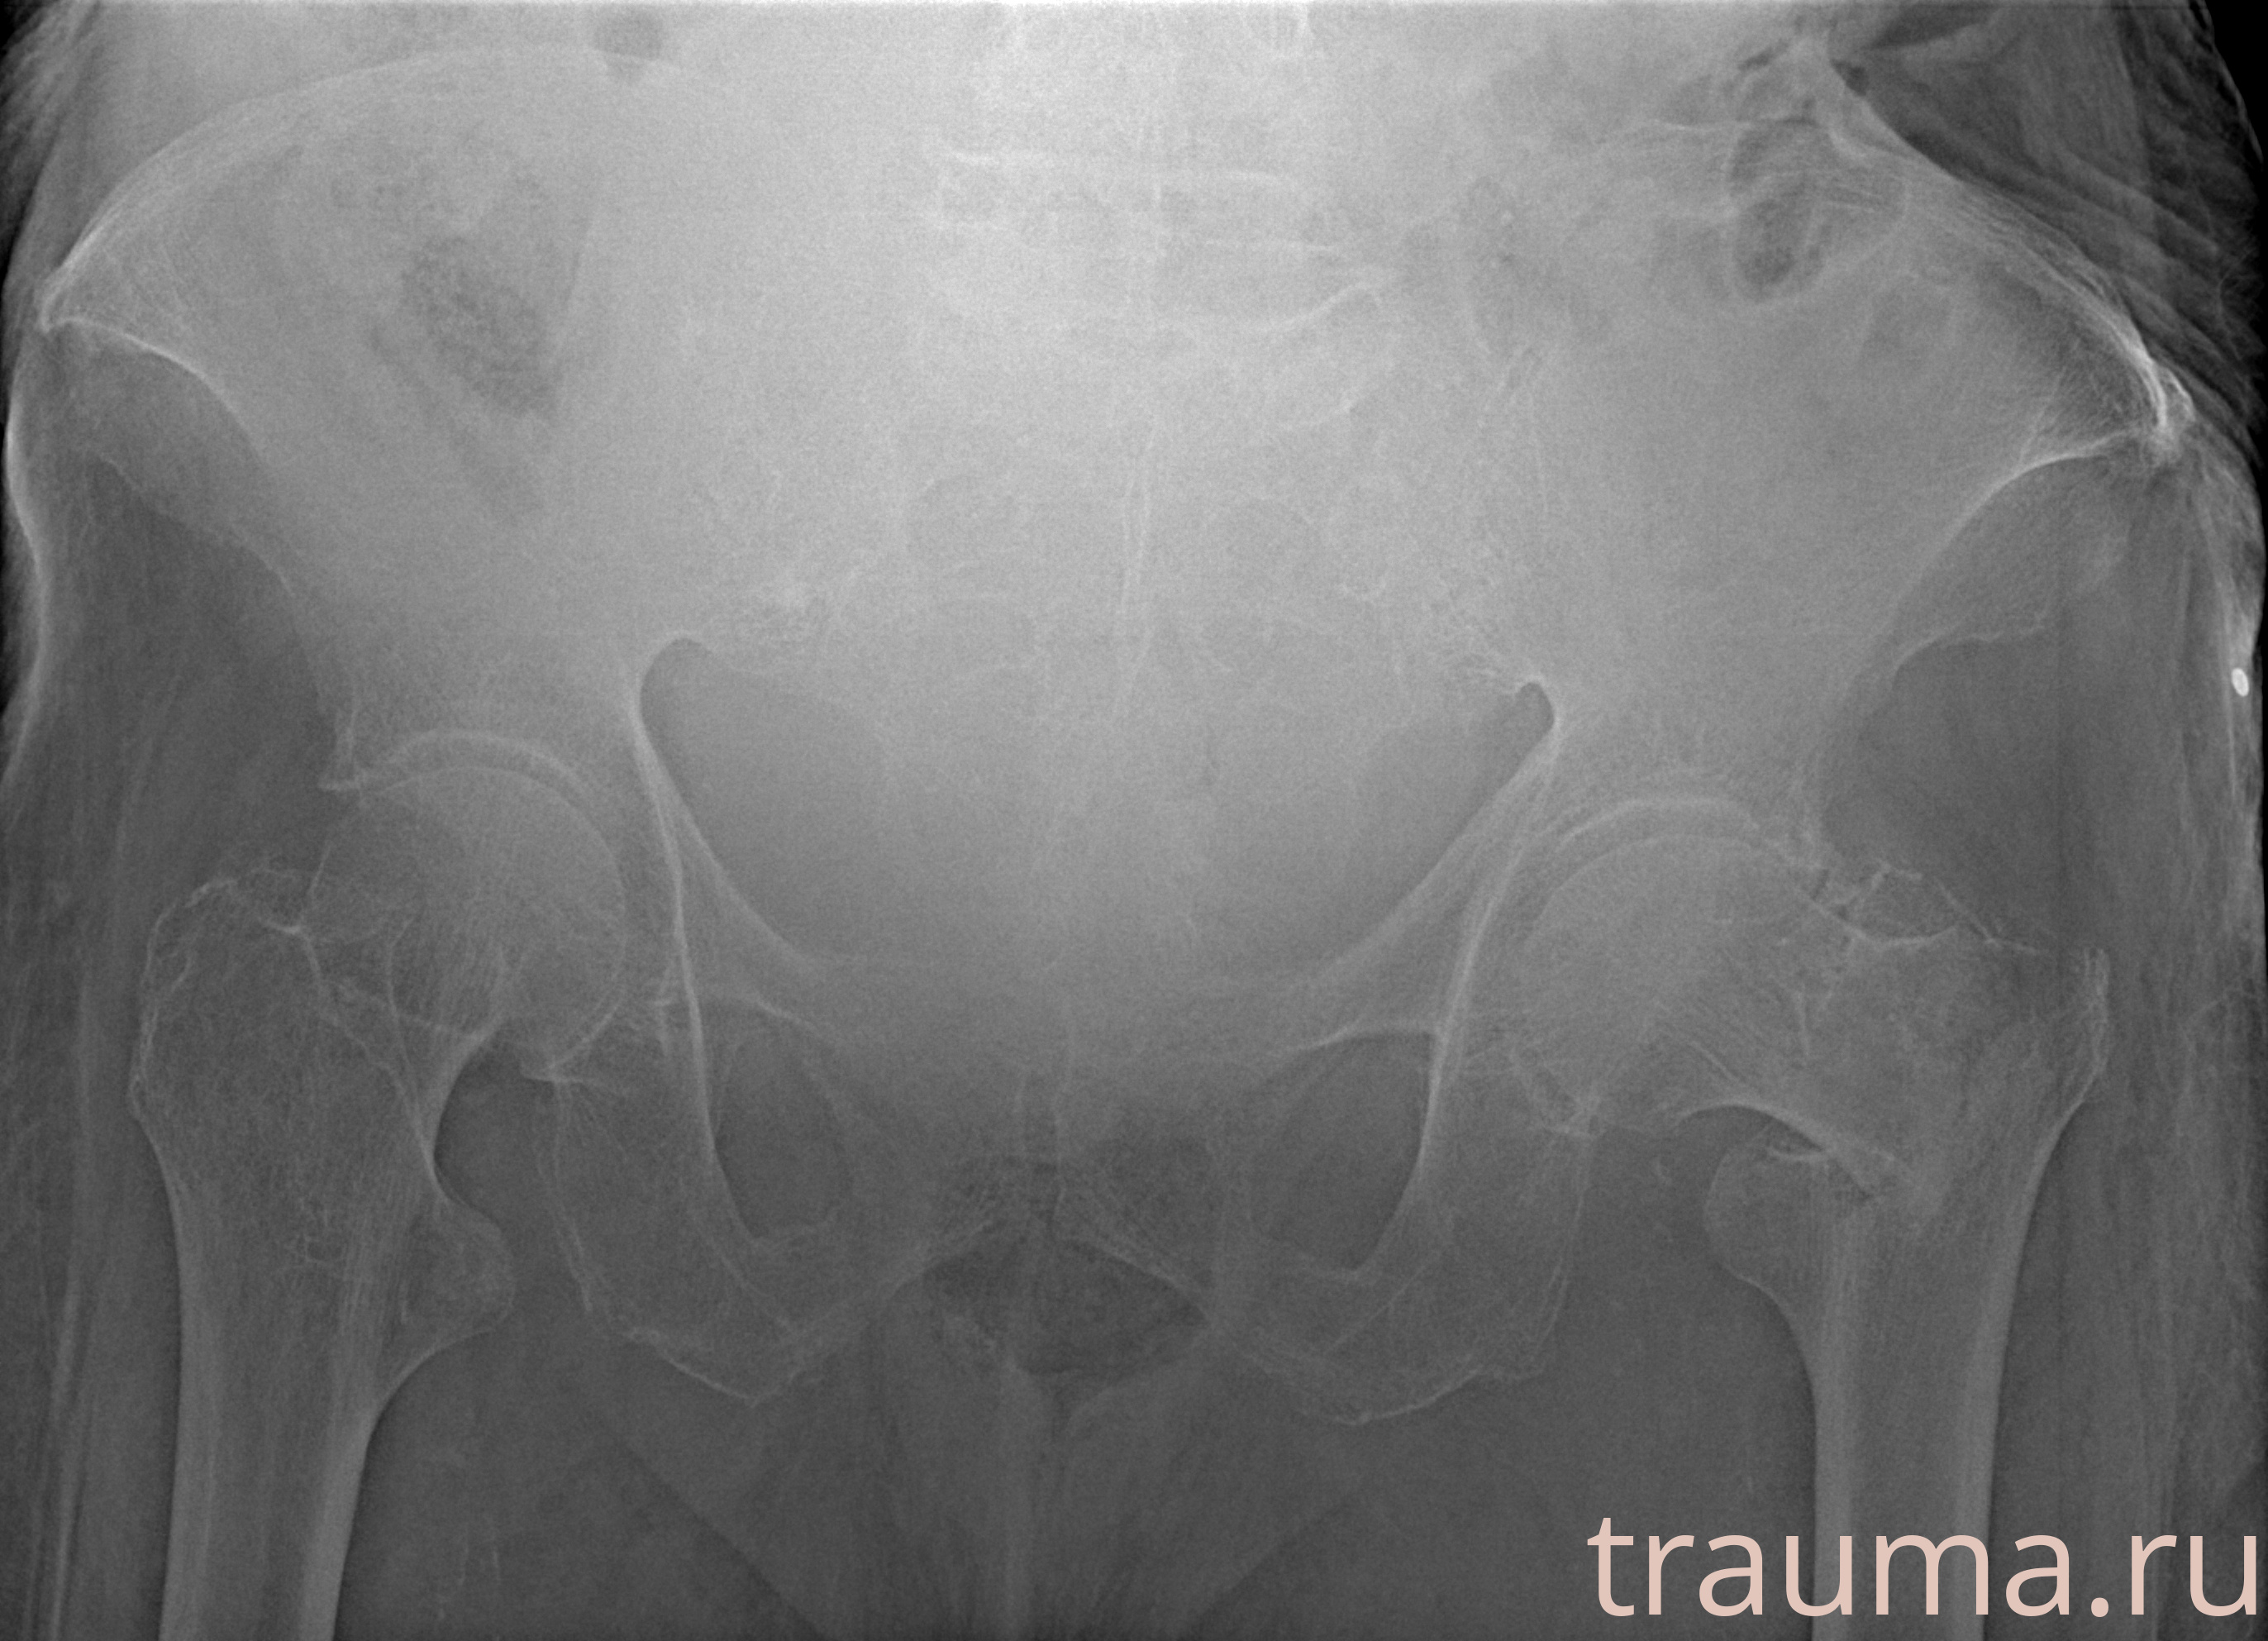

Рентгенограммы

Рентген на дому: по вашему адресу приезжает врач-рентгенолог, травматолог-ортопед с мобильным рентгеновским аппаратом, проводит диагностику травмы или заболевания, делает необходимые рентгенограммы, дает рекомендации по дальнейшему лечению. Получить качественные снимки в домашних условиях возможно благодаря уникальной методике, разработанной МосРентген Центром для института  Склифосовского

Яркость: 1   Контраст: 1   Инвертировать: 0 Увеличение: 1

Перетаскивайте мышь вверх/вниз для контраста, влево/право для яркости. Прокрутка колесом изменяет масштаб. Нажмите Сбросить для возврата к исходному изображению. При увеличении держите мышь в той области, которую хотите рассмотреть.